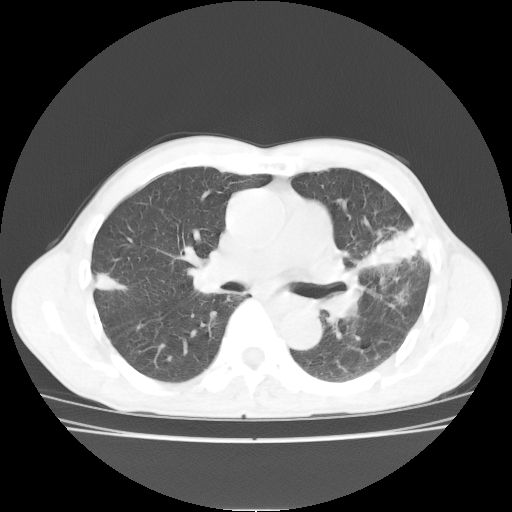

标题: CT25795:感冒后反复咳嗽两月余,痰中带血半月余。X诊断“肺 [打印本页]

标题: CT25795:感冒后反复咳嗽两月余,痰中带血半月余。X诊断“肺

1.双肺肺梗塞(理由:病灶呈三角形,与胸膜相连且局部胸膜肥厚,左心室增大)伴肺感染。

2.一元论双肺感染。

肺梗塞虽然有创意,但不现实。我考虑感染性病灶。

考虑两肺感染性病变,左肺上叶舌段肿瘤性病变待排;建议抗炎治疗后复查。